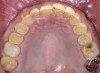

Fig 3. Preoperative occlusal view of maxillary arch.

Figure 3

A 40-year-old patient presented with the chief complaint: “My teeth are cracking, and I would like to have my original bite.” Dental findings included Class I occlusion with slight misalignment between teeth Nos. 8 and 9. Generalized severe occlusal wear and slight Class I mobility of teeth Nos. 23 to 26 were noted. Caries lesions were found on teeth Nos. 2, 4, 6, 8, 9, and 14 and abfraction lesions on teeth Nos. 4, 5, 10, 11, 13, 20, and 21. Figure 1 through Figure 3 depict the preoperative situation. Full-mouth rehabilitation was suggested. The goals for the restorative treatment were management of erosive etiology, conservation of tooth structure, and long-term protection of the restorations. A diagnostic wax-up was instrumental in determining functional and esthetic treatment goals and establishing new anterior guidance (Figure 4). A comprehensive, step-by-step treatment approach was applied, which, after periodontal pretreatment, caries control, and provisionalization, included definitive preparation (Figure 5) and restoration of the maxillary anterior teeth to establish anterior occlusal guidance. CAD/CAM–fabricated full-contour monolithic high-translucent zirconia crowns (Katana™ UTML Ultra Translucent Multi-Layered, Kuraray Noritake Dental, kuraraynoritake.com) were fabricated (Figure 6 and Figure 7) and cemented with self-adhesive resin cement (Panavia SA, Kuraray Noritake Dental). Figure 8 demonstrates the cemented anterior crowns and refined conservative preparations of posterior teeth, which were performed with minimal tooth-structure removal. High-translucent monolithic zirconia onlays and crowns were fabricated (Katana Zirconia UT, Kuraray Noritake Dental) (Figure 9 to Figure 12). The posterior restorations were adhesively bonded following the APC zirconia-bonding concept. APC-Step A involved air-particle abrasion with 50-μm aluminum oxide at 1.5 bar with a chairside microetcher (Figure 13), followed by application (APC-Step P, Figure 14) of a special ceramic primer (ClearfilTM Ceramic Primer, Kuraray Noritake) with adhesive phosophate monomers (MDP). Relative moisture and contamination control was achieved with cotton rolls and retraction cords. Rubber dam placement, which is always preferred, was difficult in this situation. The enamel surfaces of the abutment teeth were selectively etched (Figure 15) with 35% phosphoric acid (K-Etchant Gel, Kuraray Noritake Dental) and the dentin conditioned (Figure 16) with a self-etch dentin primer (Panavia V5 Tooth Primer, Kuraray Noritake Dental). A dual-cure adhesive resin (Panavia V5 Paste Universal, Kuraray Noritake Dental) was dispensed directly into the restorations with an automix syringe. The restorations were inserted, and excess cement was carefully removed (Figure 17 and Figure 18) before light polymerization (Figure 19). Postoperative views depict the treatment outcome (Figure 20 to Figure 22).